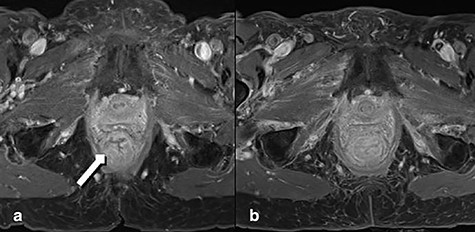

A 92-year-old woman, with known dementia and no previous history of anorectal surgery, was referred to the emergency department with a full-thickness rectal prolapse. Two months before she was diagnosed with advanced lower rectal cancer. Initially treated for hemorrhoids, a colonoscopy was arranged when patient noticed a resistance while introducing suppositories. Comorbidities were coronary heart disease and bronchial asthma. Family history was bland regarding tumor diseases. The colonoscopy demonstrated a malignant polyp of 4 cm size (3–4 cm above the anal verge). There was no clinical or endoscopic evidence of full-thickness rectal prolapse. The histology showed a moderately differentiated microsatellite-stable adenocarcinoma. A computed tomography and a magnetic resonance tomography (MRT) resulted in a cT3–T4 cN1 cM0, circumferential resection margin (CRM) positive (0 mm) staging (Fig. 1a). The multidisciplinary tumor board recommended an abdominoperineal resection. Despite detailed discussion with the patient and relatives a curative approach was declined, inter alia, because of age, comorbidities and dementia. Therefore, a palliative short-course radiotherapy with 5 × 5 Gy was performed [6].

MRT Imaging little pelvis. (a) Before radiotherapy. Tumor appears in the lower rectum with suspicion of muscle infiltration (long arrow). (b) Imaging after short-course radiotherapy.